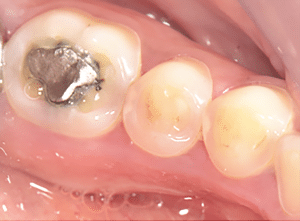

On réalise ensuite les préparations postérieures. La figure 7a est la vue initiale, la 7b la vue occlusale des préparations et la 7c la vue latérale des préparations.

Fig.7a, b, c : Préparations postérieures.

Fig.7b.

Fig.7c.

La préparation des overlays molaires consiste à retirer les anciennes préparations, à faire un biseau périphérique total sur 1-2 mm de hauteur et à hybrider, si nécessaire, les tissus dentinaires. Le biseau va permettre de créer un dôme de compression au niveau de la dent (ce qui va la renforcer), une stabilité de la pièce prothétique, un axe d’insertion unique et de mieux gérer la transition optique et esthétique (il évite d’avoir l’impression que la restauration a été « posée » sur la dent, comme un chapeau). Dans notre cas, on sait que l’augmentation de DV nous a permis de gagner 1 mm. Il n’y a donc pas besoin de réduire au moyen de la fraise la face occlusale, faisant plus de dégâts en quelques secondes que l’usure en plusieurs années…

La préparation des veneerlays est celle d’une facette sur la face vestibulaire et celle d’un overlay sur la face occlusale. Toutes ces préparations sont minimes et s’effectuent dans l’émail. Elles sont ensuite polies pour ne laisser aucune arête vive. Dans notre cas clinique, les veneerlays étaient faits « naturellement » par l’usure qui a réduit la face vestibulaire en laissant un bandeau d’émail périphérique en cervical. Il a été décidé de passer les points de contact car il y avait des débuts de déminéralisation amélaire en proximal. Sans cela, on les aurait conservés.